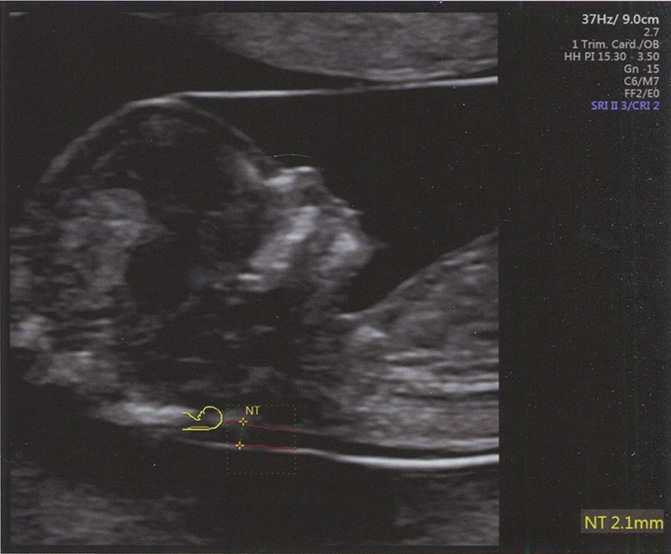

Воротниковое пространство - это ультразвуковое изображение скопления жидкости под кожей в области задней поверхности шеи плода в I триместре беременности. Правильная подготовка специалистов, проводящих ультразвуковое исследование, и строгое соблюдение установленных единых методических рекомендаций по ультразвуковой оценке ТВП лежат в основе точного (то есть с минимальным разбросом показателей) измерения этого параметра разными операторами. Получение качественного ультразвукового изображения в определенной плоскости способствует повышению точности измерения ТВП (рис. 1.1). С целью уменьшения погрешностей, возникающих при работе разных специалистов, некоторые производители ультразвукового оборудования предлагают полуавтоматический метод оценки ТВП (рис. 1.2). В табл. 1.1 приведены все существующие на сегодняшний день критерии правильного измерения ТВП. Роль оценки ТВП в выявлении анеуплоидий обсуждается в главе 6.

Рис. 1.2. Ультразвуковое изображение среднесагиттального среза головы плода в 12 нед беременности, демонстрирующее полуавтоматическое измерение ТВП. При использовании полуавтоматического режима оператор помещает контур для выделения зоны интереса (dash box) на область воротникового пространства, соответствующая программа распознает наибольший размер ТВП и размещает калиперы. Этот метод уменьшает субъективность измерений ТВП и повышает их точность. В данном случае ТВП составляет 2,1 мм.